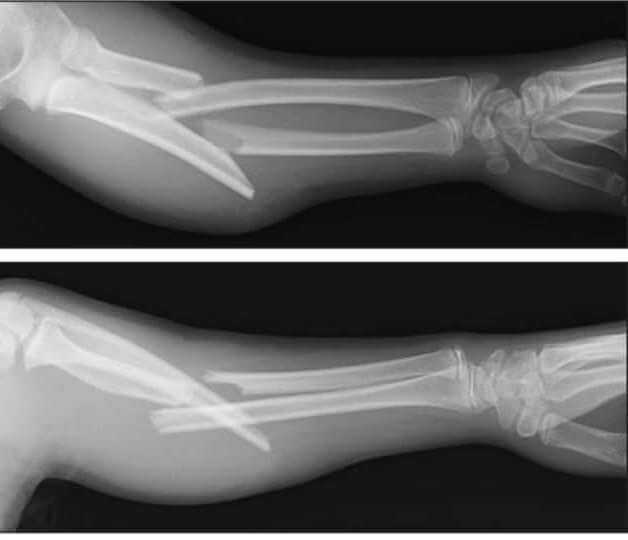

6. Монтеджа. При этой травме страдает верхняя треть диафиза локтевой кости. Травма сопровождается вывихом головки лучевой кости. Нарушение обусловлено падением на согнутую конечность. Нередко наблюдается поражение локтевого нерва. Перелом Монтеджа бывает сгибательным и разгибательным.

7. Галеацци. При этой травме наблюдается повреждение нижней трети лучевой кости. Для нее характерен вывих лучелоктевого сочленения. Ключевой причиной проблем становится удар каким-то предметом по области предплечья. А также травма может быть обусловлена падением на руку. При ее получении смещаются костные отломки лучевой кости вперед. При этом головка локтевой кости отклоняется вперед или назад.